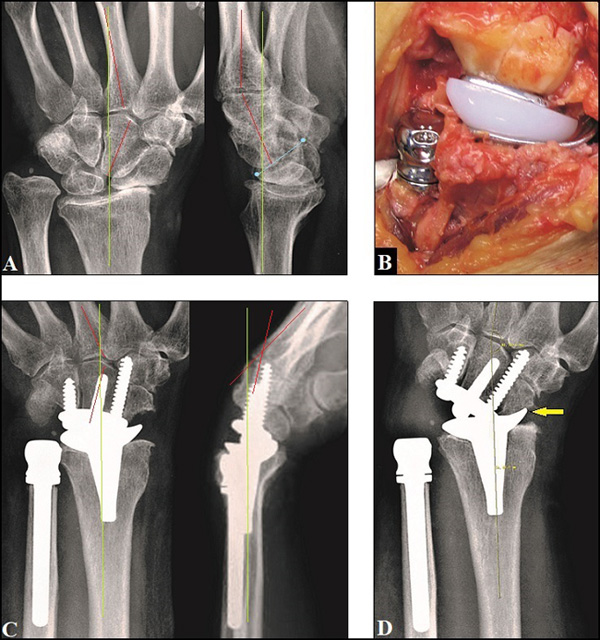

Wrist with a SNAC III lesion. (A) Final radiograph of four-corner …

35 Pyrocarbon Scaphoid Implant Allowing Adaptive Mobility in Proximal …